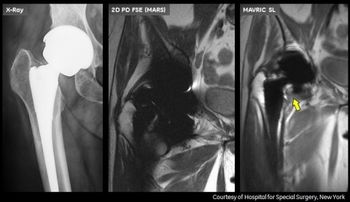

GE Healthcare this week introduced a new MRI technique designed to allow for more accurate imaging of soft tissue and bone in patients with metal joint implants.